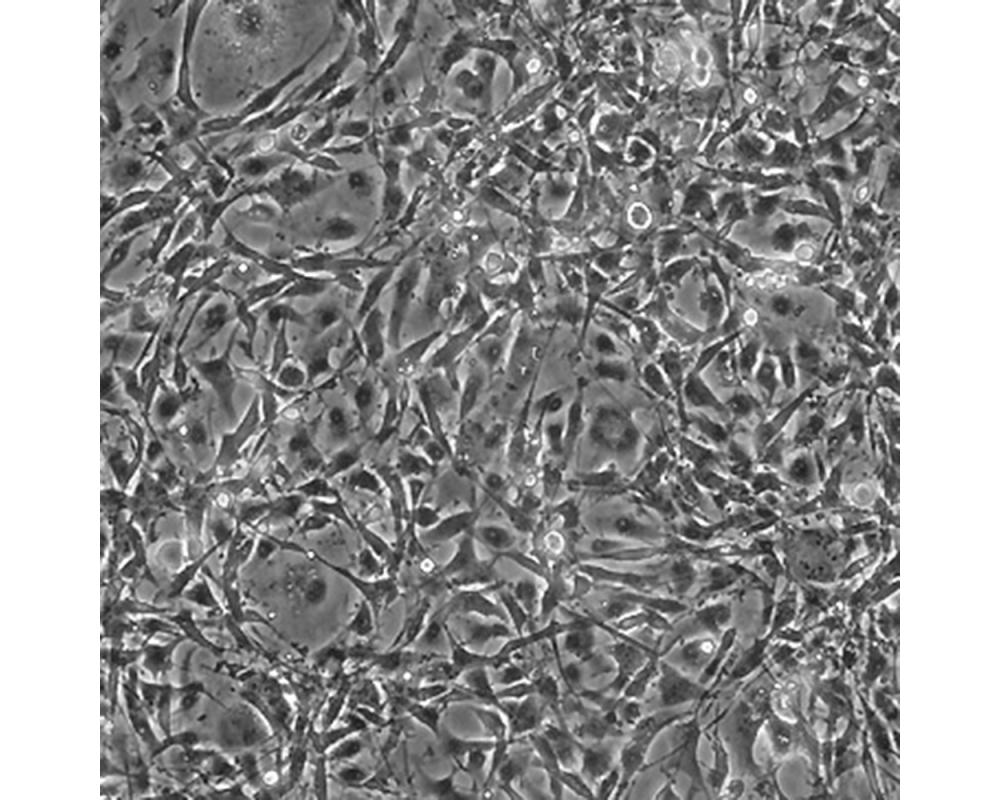

U-118 MG

中文名稱 人腦星形膠質(zhì)母細胞瘤

組織來源 星形膠質(zhì)母細胞瘤;男性

生長特性 adherent

形態(tài)特征 mixed

細胞描述 注意: 據(jù)報道來自不同個體的膠質(zhì)母細胞瘤細胞株U-118 MG (HTB-15) 和 U-138 MG (HTB-16)有著一致的VNTR和相近的STR模式。 U-118 MG 和 U-138 MG細胞遺傳學(xué)上很相似并有至少六個衍生標(biāo)記染色體。 這是1966年至1969年間J. Ponten和同事從惡性神經(jīng)膠質(zhì)瘤中構(gòu)建的細胞株中的一株(其它包括ATCC HTB-14和 ATCC HTB-16 and ATCC HTB-17)。 1987年用BM-Cycline培養(yǎng)6周去除了支原體污染。